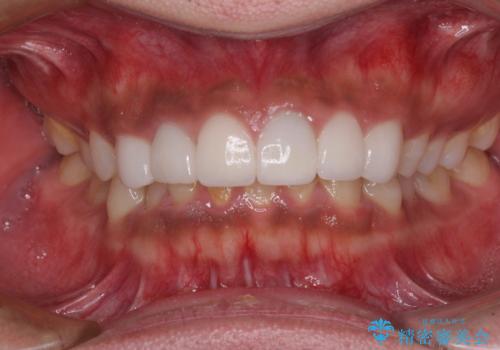

欠けてしまった前歯のセラミック 同じ色合いで再製作

- 前歯のセラミッククラウンが欠けてしまったとのことで来院された患者様です。

周りの他の歯もセラミッククラウンやラミネートベニアが装着されていたため、欠けてしまったクラウンを丁寧に取り外し、同じような色合いとなるように製作することとしました。

欠けたセラミッククラウンを丁寧に外して技工所に送ったことで、元のセラミッククラウン同様の色合いとなり、自然な仕上がりとなりました。